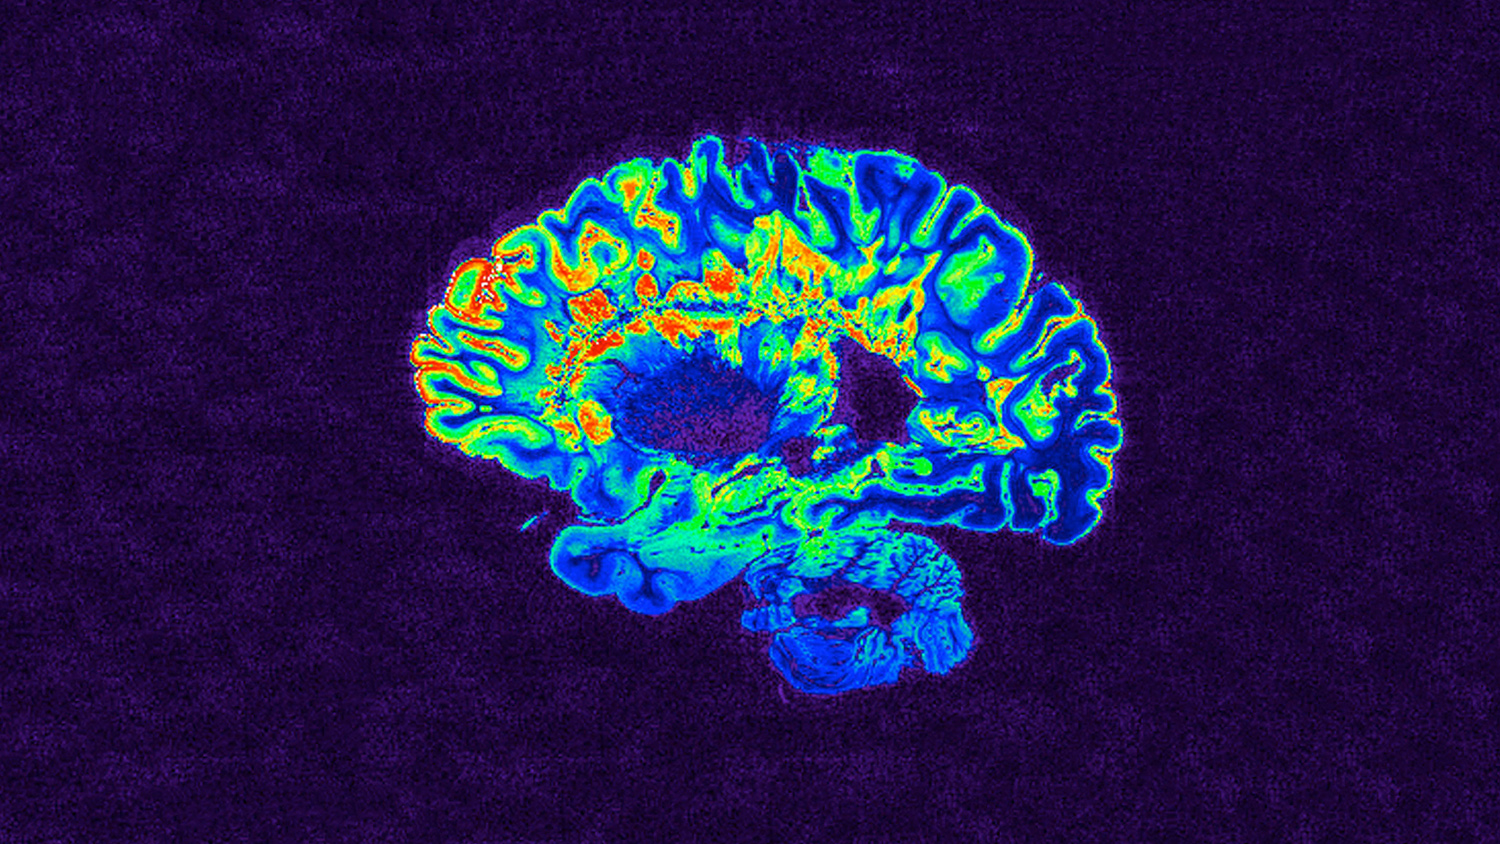

An MRI scan shows the brain of a person with multiple sclerosis. Image by NIH